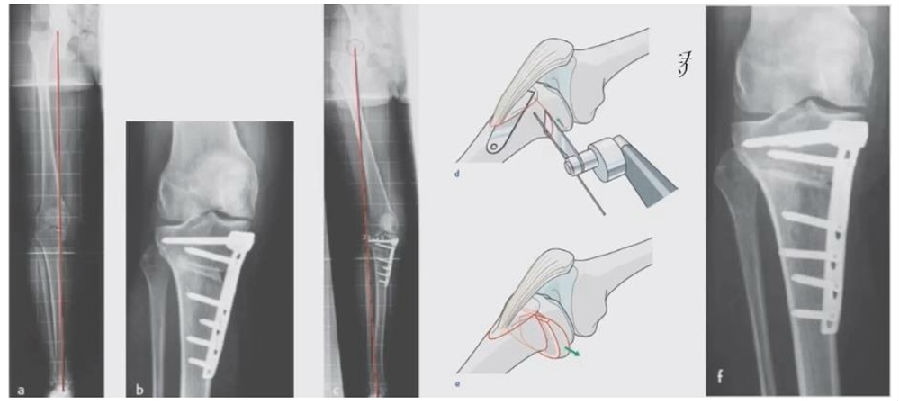

1、综合判断力线的方法

现在对于力线的判断大致通过以下几方面:①大体形态;②透视确定力线,连接股骨头中心、踝关节中心,看力线杆和膝关节中心的位置关系;③MPTA(胫骨平台关节线和胫骨侧机械轴夹角);④PSI。

1、原因及预防

(1)肢体外旋

一般来说在麻醉状态下肢体会处于外旋位,此时去测定力线的话往往需要将肢体放在旋转中立位,但是在内旋肢体的过程中会出现内翻应力,那么这种情况下判断力线会带来误差,所以通常建议大家要把手术床做一点旋转,让患肢处于自然的旋转中立位,这样再去判断力线就比较准确。

(2)MCL浅层未彻底松解

对于MCL,大多数忽视的是后侧束,如果不能把后侧束彻底松解,那么在撑开过程中往往会感觉撑不开,此时如果过度去撑开的话,会导致在关节内侧出现很大的压力,所以这时对力线会产生一定的误导。

(3)力线验证未模仿负重应力

现在所谓的目标力线应该是模仿负重时的力线。做截骨时,通常会将力线轻度外移,如果没有考虑关节内畸形、韧带松弛或是软骨磨损,那么在负重时,在内侧副韧带撑开过程中,会出现力线偏移。所以要注意,手术中间在调整目标力线时,要以应力状态下为标准。

(4)拉力螺钉加压过度

拉力螺钉的过度使用可能会引起矫形位置的角度丢失。当拉力过度时,会将力线由内侧向外侧轻度拉回,使力线丢失一部分,所以切忌过度使用。

2、处理

(1)如果在手术台上,或是刚做完手术就发现矫正不良问题,此时比较简单。需要先跟患者进行沟通,在手术中直接将远端4颗螺钉卸下来,调整好力线后重新打入即可。但是注意要把远端单皮质螺钉换成双皮质螺钉。

(2)如果患者已经达到初始愈合,此时如果出现过度外翻,需要在内侧重新做内侧闭合楔。

(3)如果做完手术时间较长,出现过度矫正或矫正不足时,需要重新做力线分析,看一看力线在哪个方向可以再进行调整。胫骨侧有调整余地,就在胫骨侧进行调整;股骨侧需要调整,就在股骨侧进行调整。